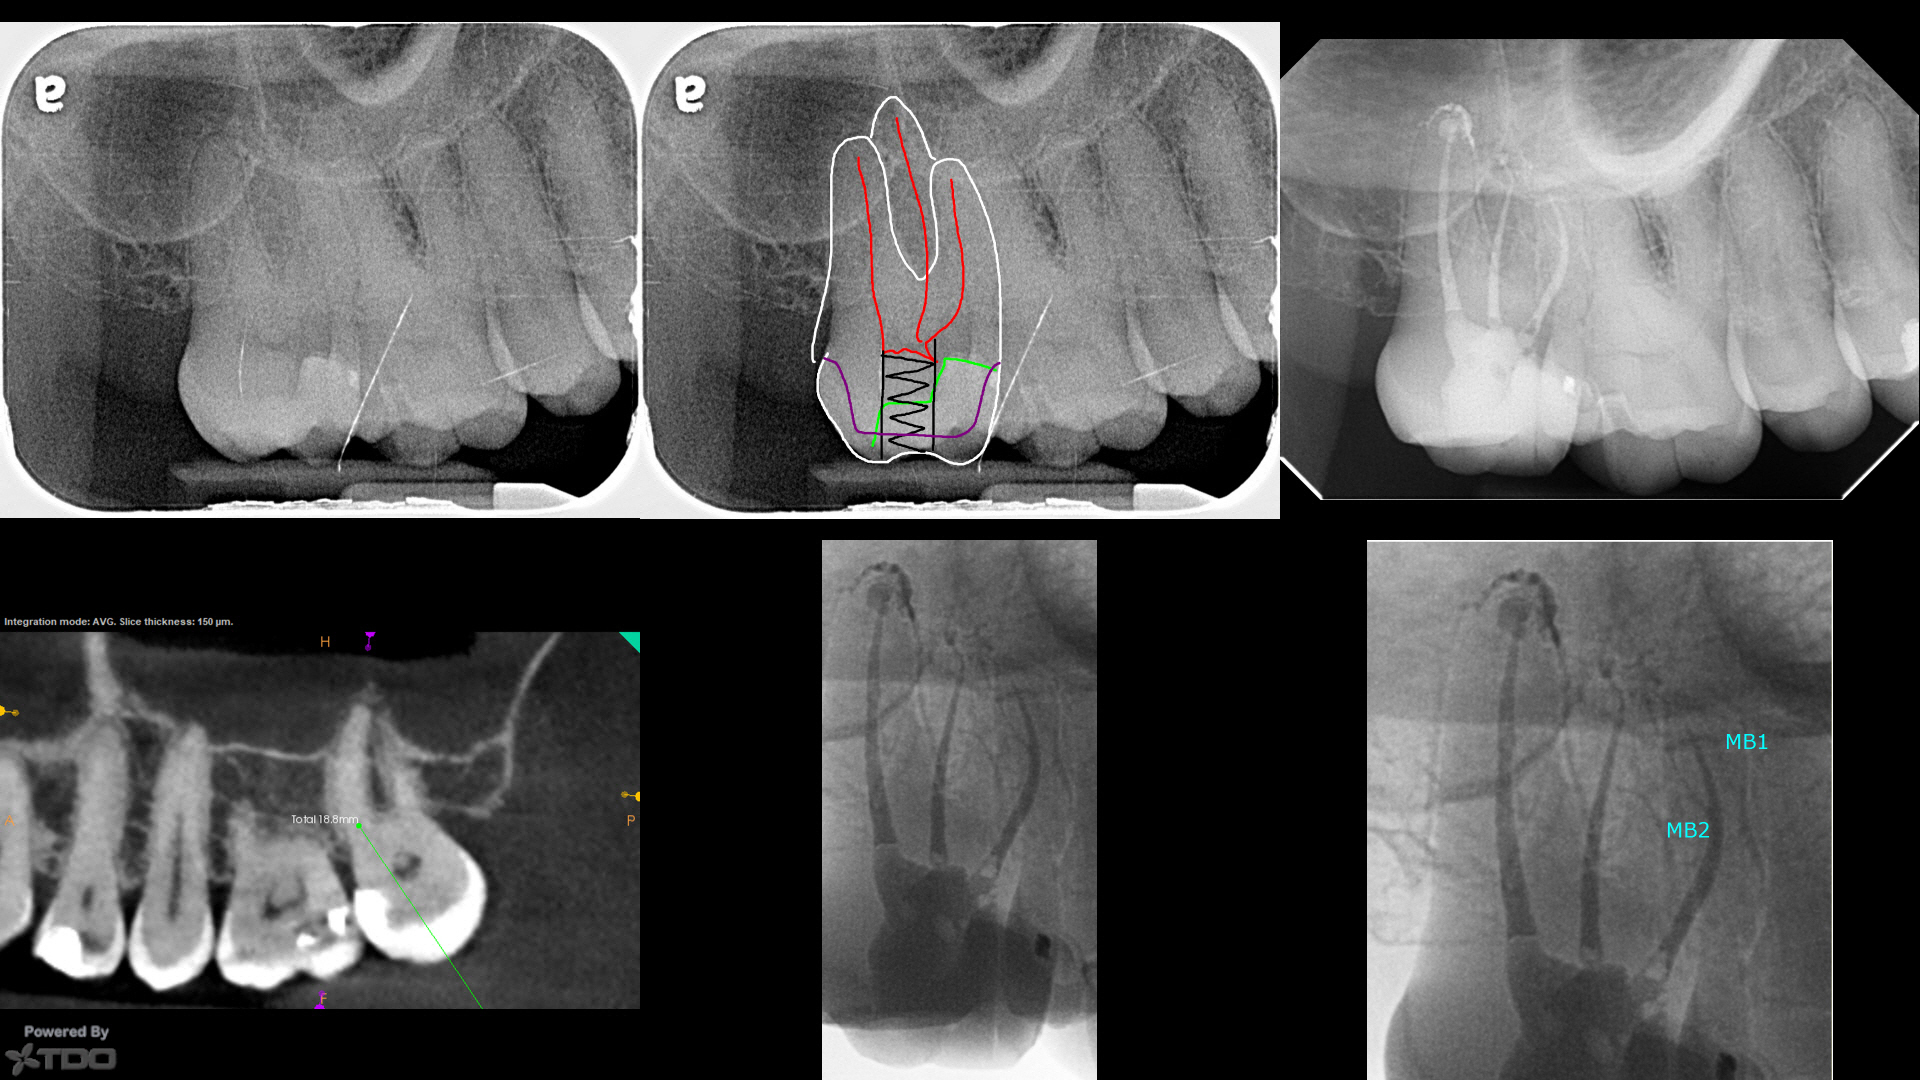

How to Endodontics The State of the Art PDF) Special Issue “The State of the Art in Endodontics”の詳細情報

PDF) Special Issue “The State of the Art in Endodontics”。APEXIFICATION USING MTA- A CASE SERIES。State of the art and science of endodontics - ScienceDirect。

商品説明

「HowtoEndodonticsTheStateoftheArt」